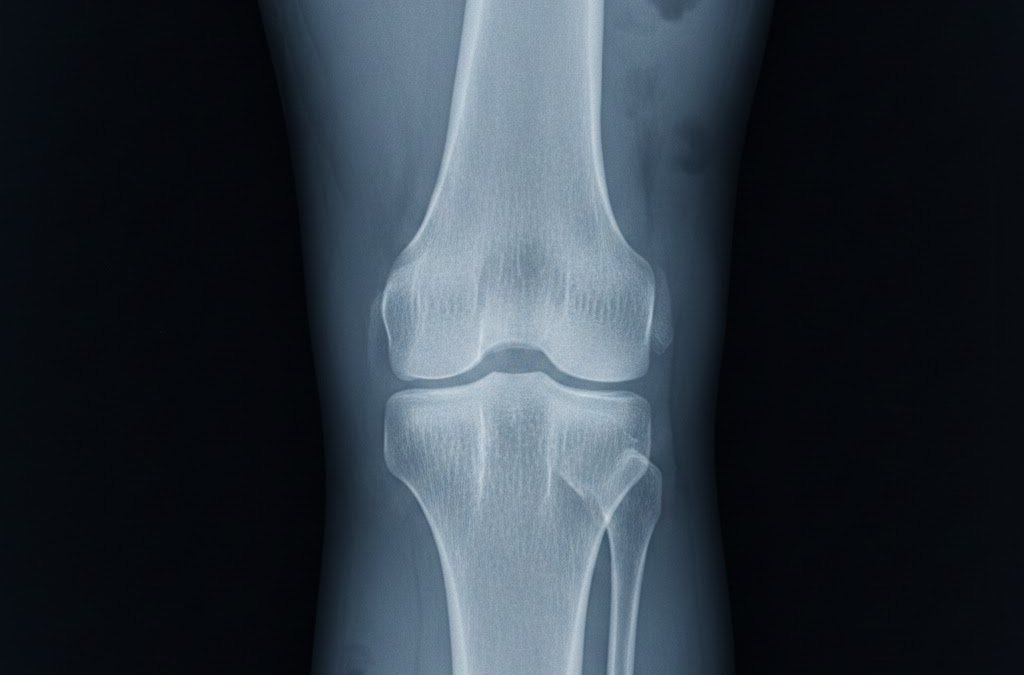

Arthritis is a broad term for conditions that cause inflammation in the joints. The most common form, osteoarthritis (OA), occurs when the cartilage—the protective cushion between bones—gradually wears down. As cartilage deteriorates, bones may rub against each other, leading to pain, stiffness, swelling, and reduced range of motion.

“Bone-on-Bone” is a term often used to describe the advanced stage of OA. In this stage, cartilage is completely worn away, causing the bones in the joint to rub directly against each other. This can lead to: